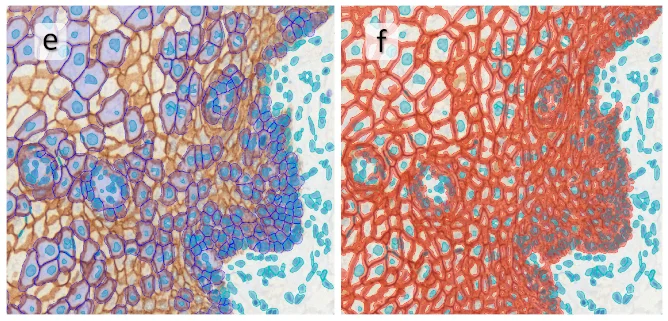

Image (b) shows detected nuclei, covered by nuclei mask in light blue. Next only membranes were detected (c), which are shown in green; (d) shows the detection of the whole E-cadherin+ epithelial tissue, also marked in green.

In image (e) only cells with nuclei are identified, and the whole cell with the membrane is shown in blue, while the nuclei are covered by the light blue nuclei mask; (f) represents the nuclei in light blue and the total membranes in red.